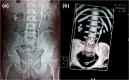

Fig. 1

a Plain X-ray showing a stent forgotten for 23 years in a 63-year-old patient, completely calcified. b Same patient as in (a), showing 3-D reconstruction of the NCCT showing severe encrustations along the entire length of the stent